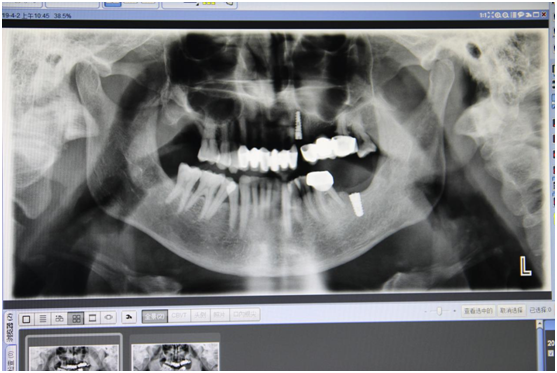

术前

22